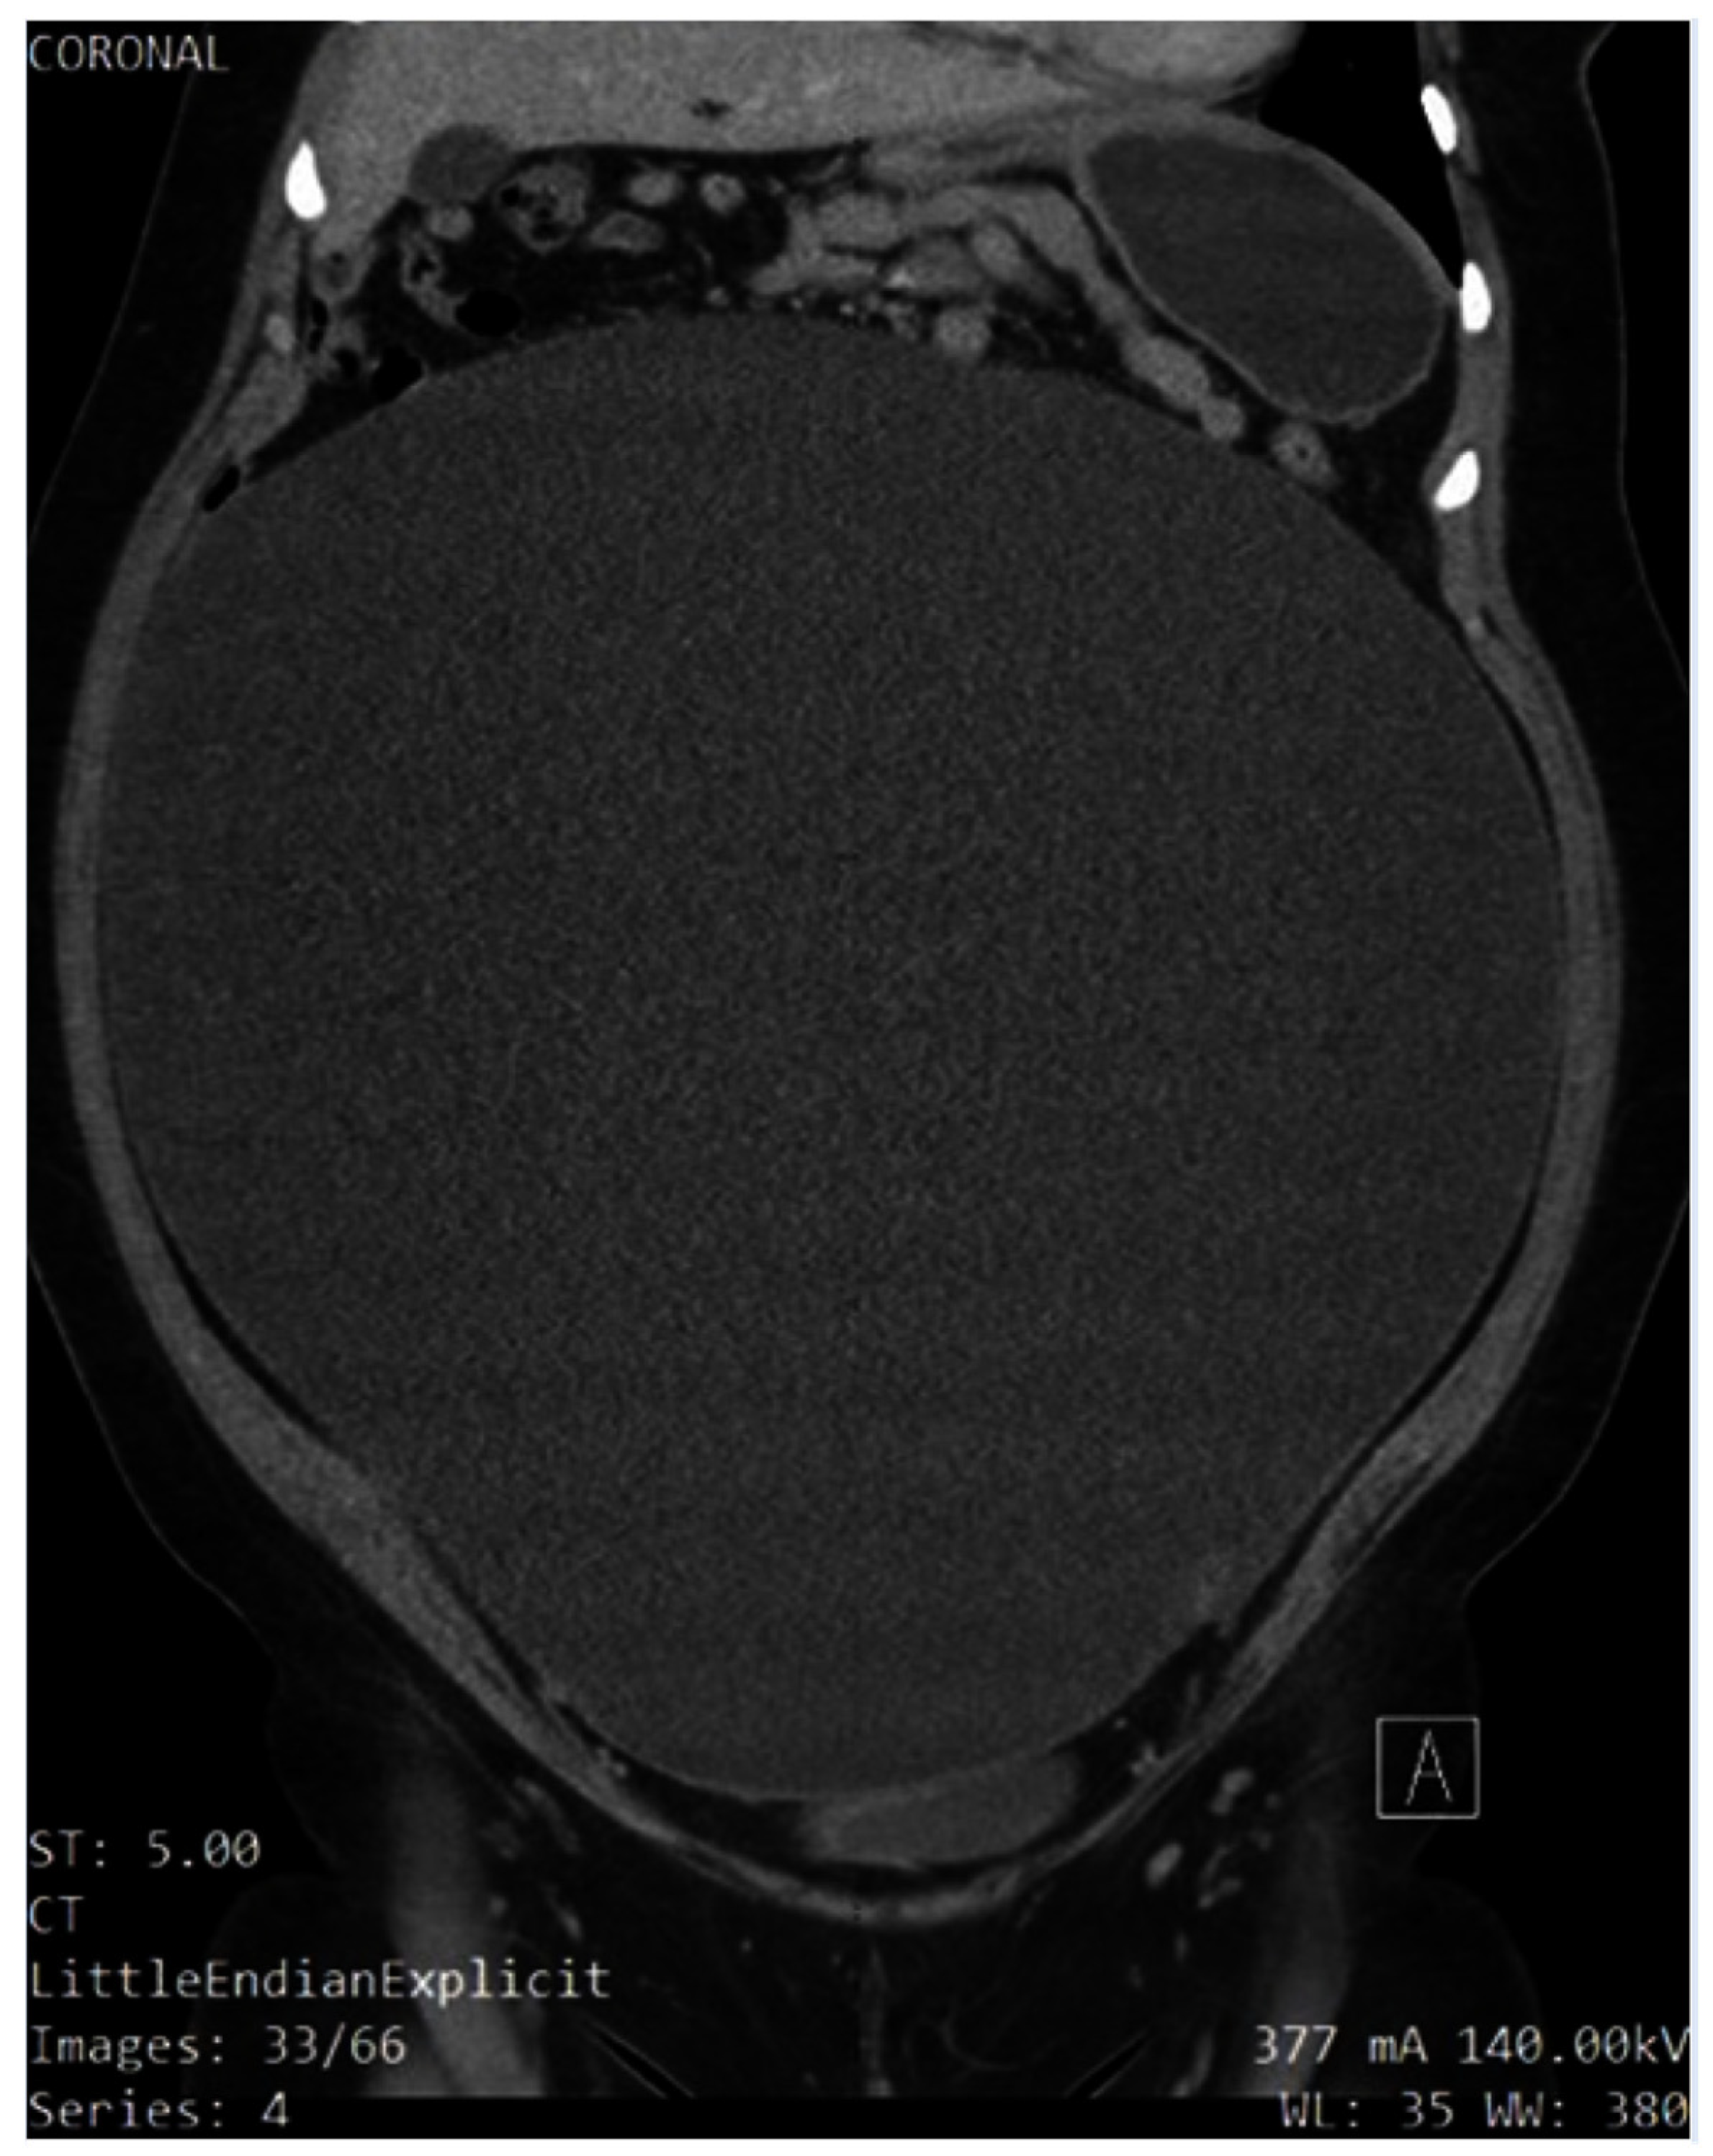

A pelvic ultrasound reported a normal uterus with no endometrial abnormalities, and the right ovary appeared normal. The left ovary was not visualized (Figure 1 and Figure 2). Additionally, the origin of the large cystic structure was unknown. An abdominal/pelvic computerized tomography (CT) with contrast found a 36 cm cyst lesion filling the abdominal and pelvic cavity which appeared to originate from the left adnexa with a complicated hyperdense fluid or debris focus inferiorly (Figure 3). The surrounding structures appeared unremarkable. There was a trace amount of fluid in the Douglas pouch (Figure 4).

Figure 4. Coronal slice of non-contrast CT of abdomen demonstrating the compression of the neighboring structures up to the thoracic cavity, which explains some of the patient’s symptoms, such as shortness of breath.